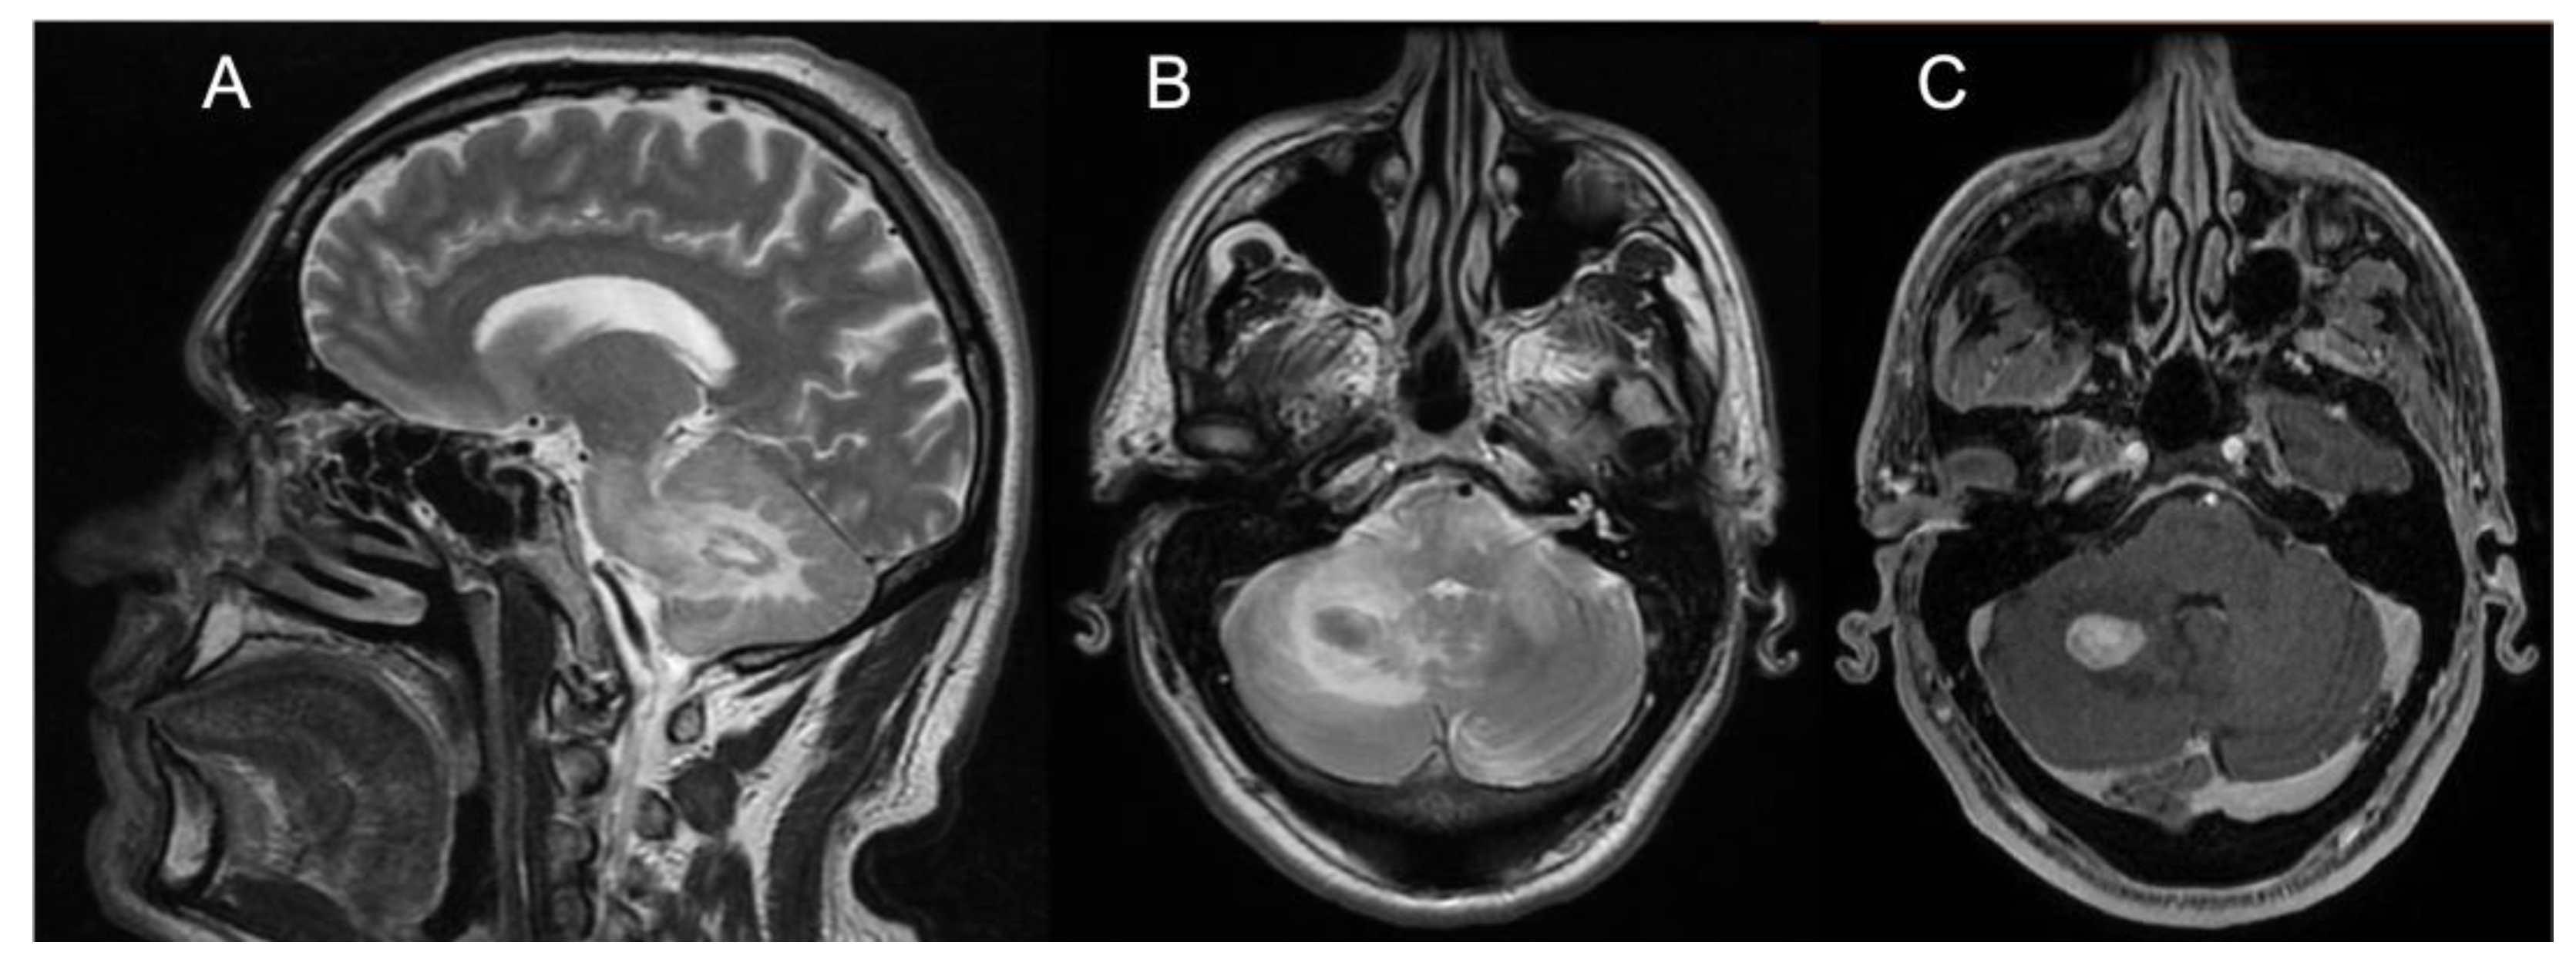

Brain MRI showed T2/FLAIR hyperintense signal alterations without contrast enhancement variably involving the white matter of cerebellar hemispheres, middle cerebellar peduncles, dentate nuclei, pons, and midbrain and cerebral peduncles in all cases (Figure 1). Three patients (Pts 1, 2, 4) also presented similar supratentorial T2/FLAIR hyperintensities variably involving the paratrigonal area, posterior arm of the internal capsule, globus pallidus, peri-aqueductal, and parahippocampal areas, with evidence of gadolinium contrast enhancement in the paratrigonal area not shown in Pt 3. Moreover, signs of cerebellar atrophy and bilateral hypointense signal abnormalities in basal ganglia on SWI sequences, suggestive of iron deposition, were evident in Pts 1, 3, and 4 (Figure 1). Of note, in Pt 2 manifesting a subacute neurological outcome, MRI also showed two nodular lesions (30 × 20 × 20 mm3) in the right cerebellar hemisphere with contrast enhancement (Figure 2) and elevated levels of r-CBV (regional cerebral blood volume) on the perfusion study and DWI-restriction, indicative of hypercellularity. Finally, Pt 3, affected by diabetes insipidus, also presented an empty sella. Signs of paranasal sinuses or mastoid inflammation were evident in three patients (Pts 1, 2, and 3). Spinal cord MRI was normal in all patients.

Figure 2. Panel showing brain MRI of Patient #2. (A) Sagittal T2-weighted scan showing one nodular lesion along with extensive hyperintensity of the white matter of the RCH, the ipsilateral MCP, and the pons. (B) Transverse T2-weighted scan (pons level) showing the same nodular hypointense lesion with hyperintensity of the white matter of the RCH, both MCPs and the pons. (C) Transverse T1-weighted scan (pons level) showing marked, homogeneous contrast enhancement of the RCH nodular lesion. Abbreviations: RCH: right cerebellar hemisphere; MCP: middle cerebellar peduncle.

Brainsci 13 00026 g002